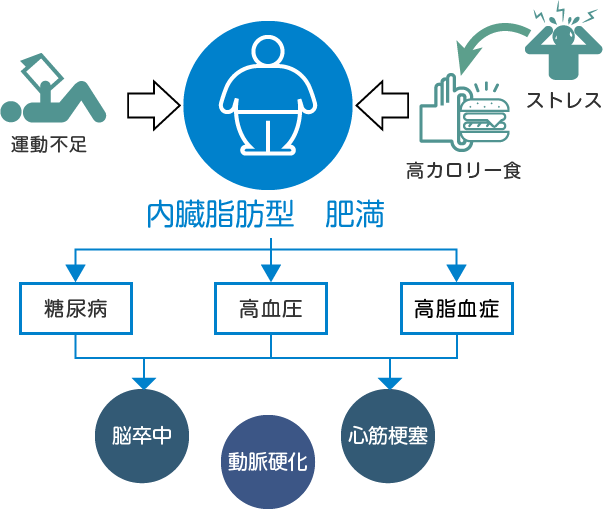

さかもと内科 消化器クリニック 生活習慣病